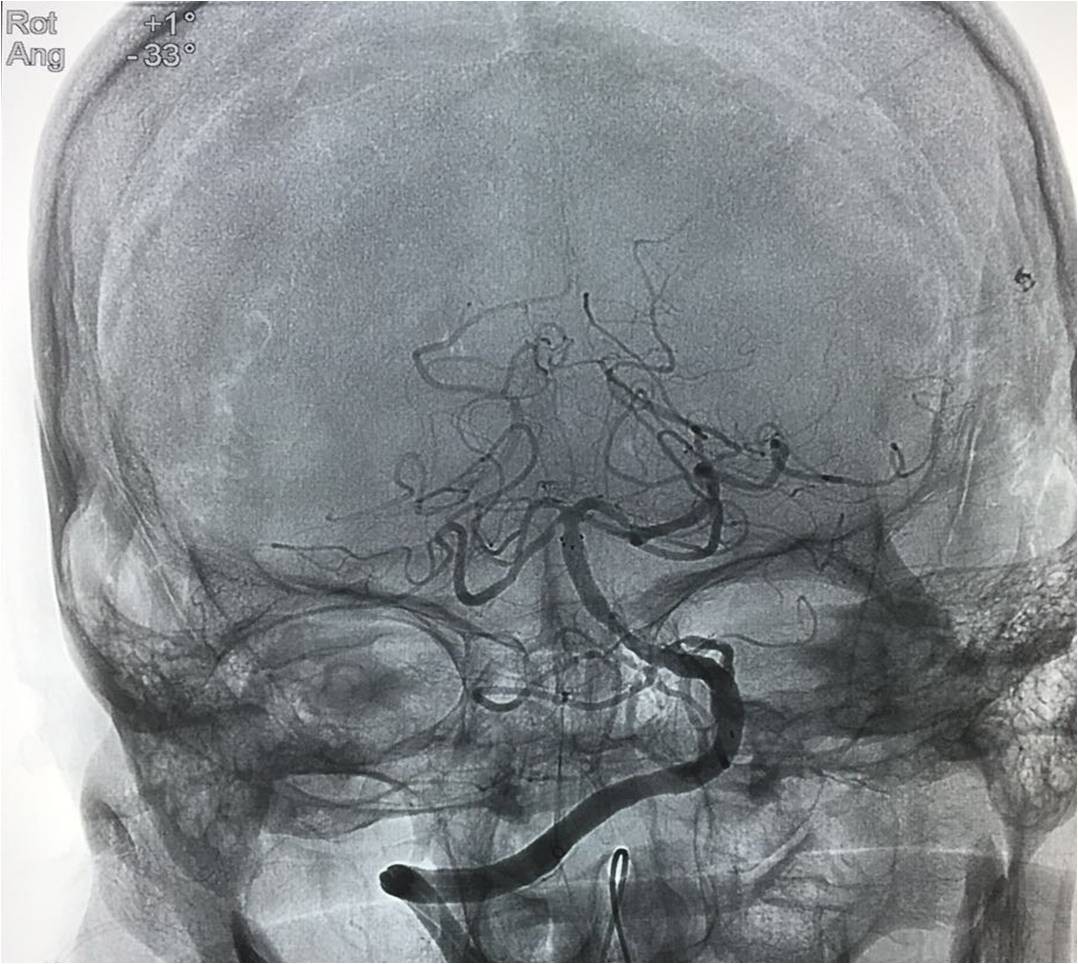

▼将Solitaire FR 送进微导管后将支架至于闭塞。部位远端,定位释放支架,保持原位5-10分钟后,将支架和微导管同时回撤。

▼复查造影。